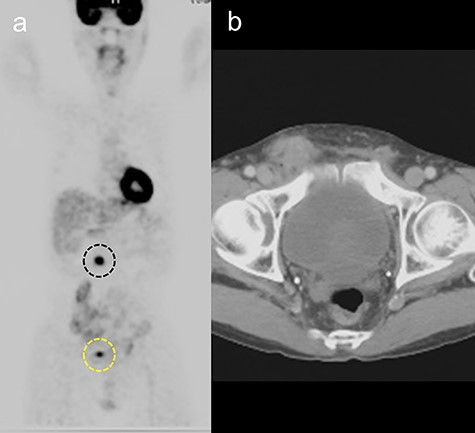

A 65-year-old man was admitted for the treatment of transverse colon cancer. He had a history of bilateral hernioplasty with mesh-plugs 6 years previously at another hospital. He had no complaints or findings on physical examination referable to the hernia repair. Fluorine-18 fluorodeoxyglucose positron emission tomographic (PET) scan showed positive findings in the transverse colon and in the right inguinal region prior to colon resection (Fig. 1a). Computed tomographic (CT) scan revealed a mass with indistinct margins in the same area highlighted on the PET scan (Fig. 1b). Inguinal lymph node metastasis was suspected and ultrasound-guided fine-needle biopsy performed, which showed no evidence of malignancy. After transverse colon resection, he was followed up with CT scans performed every 6 months. For three and a half years after the colon resection (Nine and a half years after hernia repair), the right inguinal region showed progressive changes (Fig. 2a–c). At 1 year after colon resection (7 years after hernia repair), fluid retention was observed, but by the second year (8 years after hernia repair), it was slightly reduced. After three and a half years after colon resection (nine and a half years after hernia repair), the fluid had resorbed completely, similar to the findings at 6 years after hernia repair. The patient had no complaints referable to the right inguinal region during follow-up.

(a) Fluorine-18 fluorodeoxyglucose positron emission tomographic scan showing positive findings in the transverse colon (black dotted line) and right inguinal area (yellow dotted line). (b) Computed tomography scan showing a mass with indistinct margins in the right inguinal area, 5 years after hernia repair.